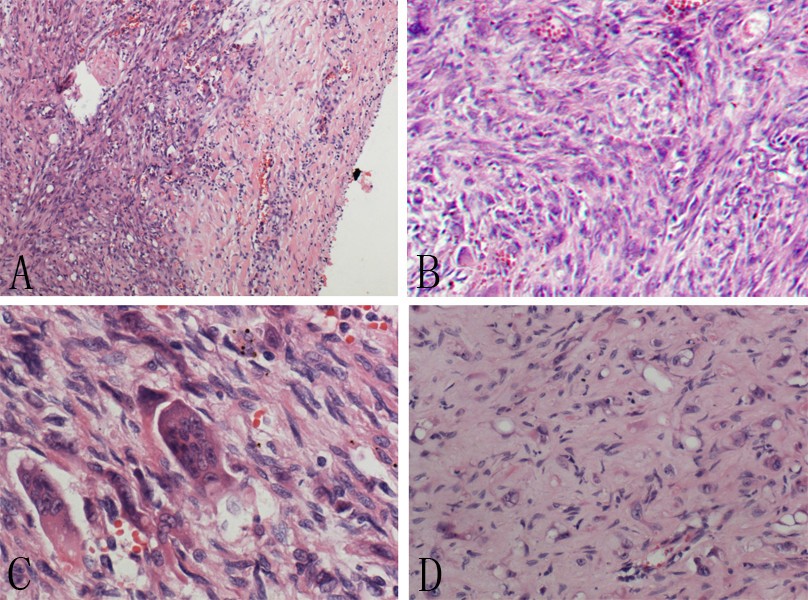

Photomicrographs reveal histological features of malignant fibrous Spindle Cell Histiocytoma [1] it can affect soft tissues, bones, retroperitoneum, and. Cellular fibrous histiocytoma differs from classical benign fibrous histiocytoma by several key histological features: Mesenchymal stem cells are the most likely origin of the tumor, instead of histiocytes as previously thought. There is debate as to whether dermatofibroma. Spindle cell neoplasms arising in the skin comprise a heterogeneous group of tumors. Spindle Cell Histiocytoma.